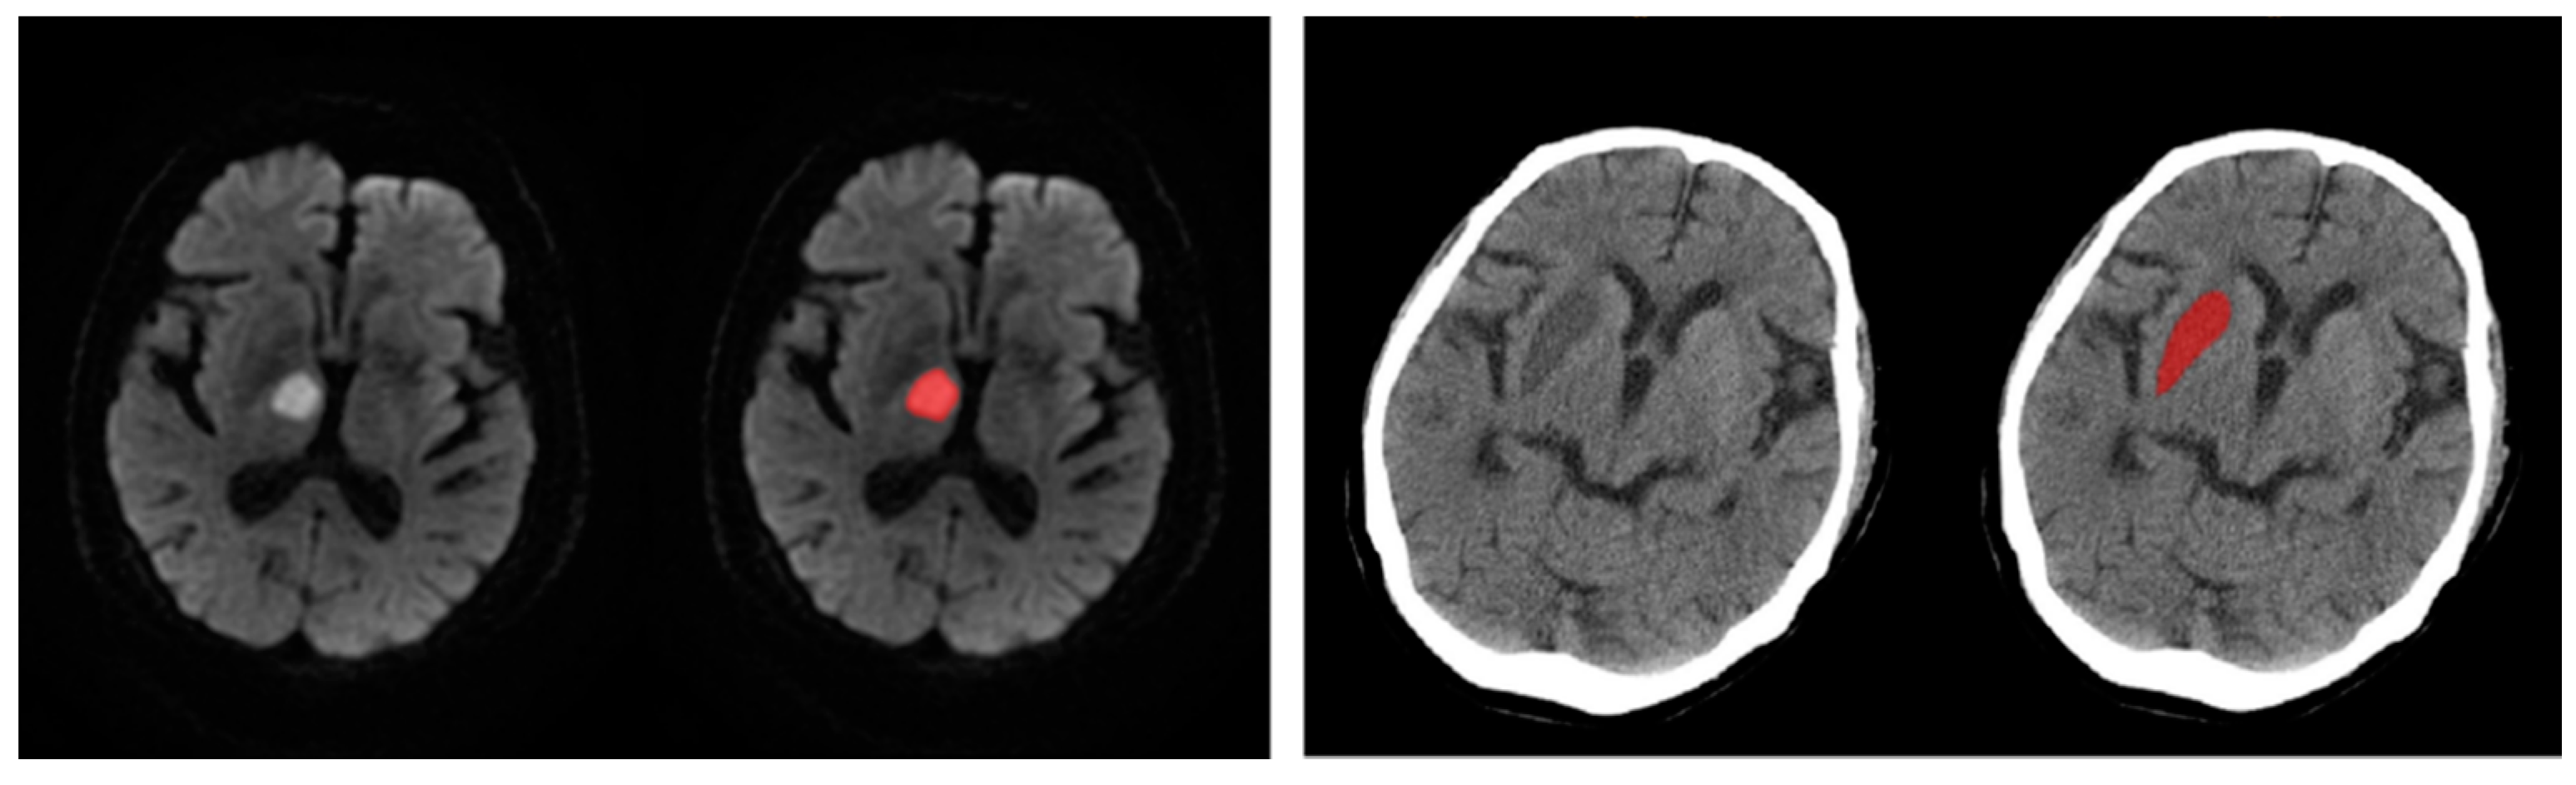

2.3. Imaging Processing